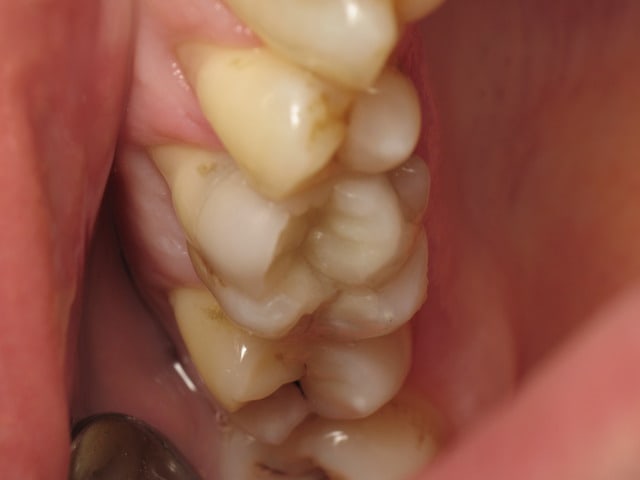

un cas de ce matin.

-avec, IDS (immediate dentin sealing) très pratique pour avoir une étanchéité le jour de la préparation, aurais pu/du se faire sous digue....

- Collage avec composite de stratification chauffé et vibré, très facile pour gérer les excès ...

- Permettra de comparer le vieillissement de l'onlay versus composite direct ...